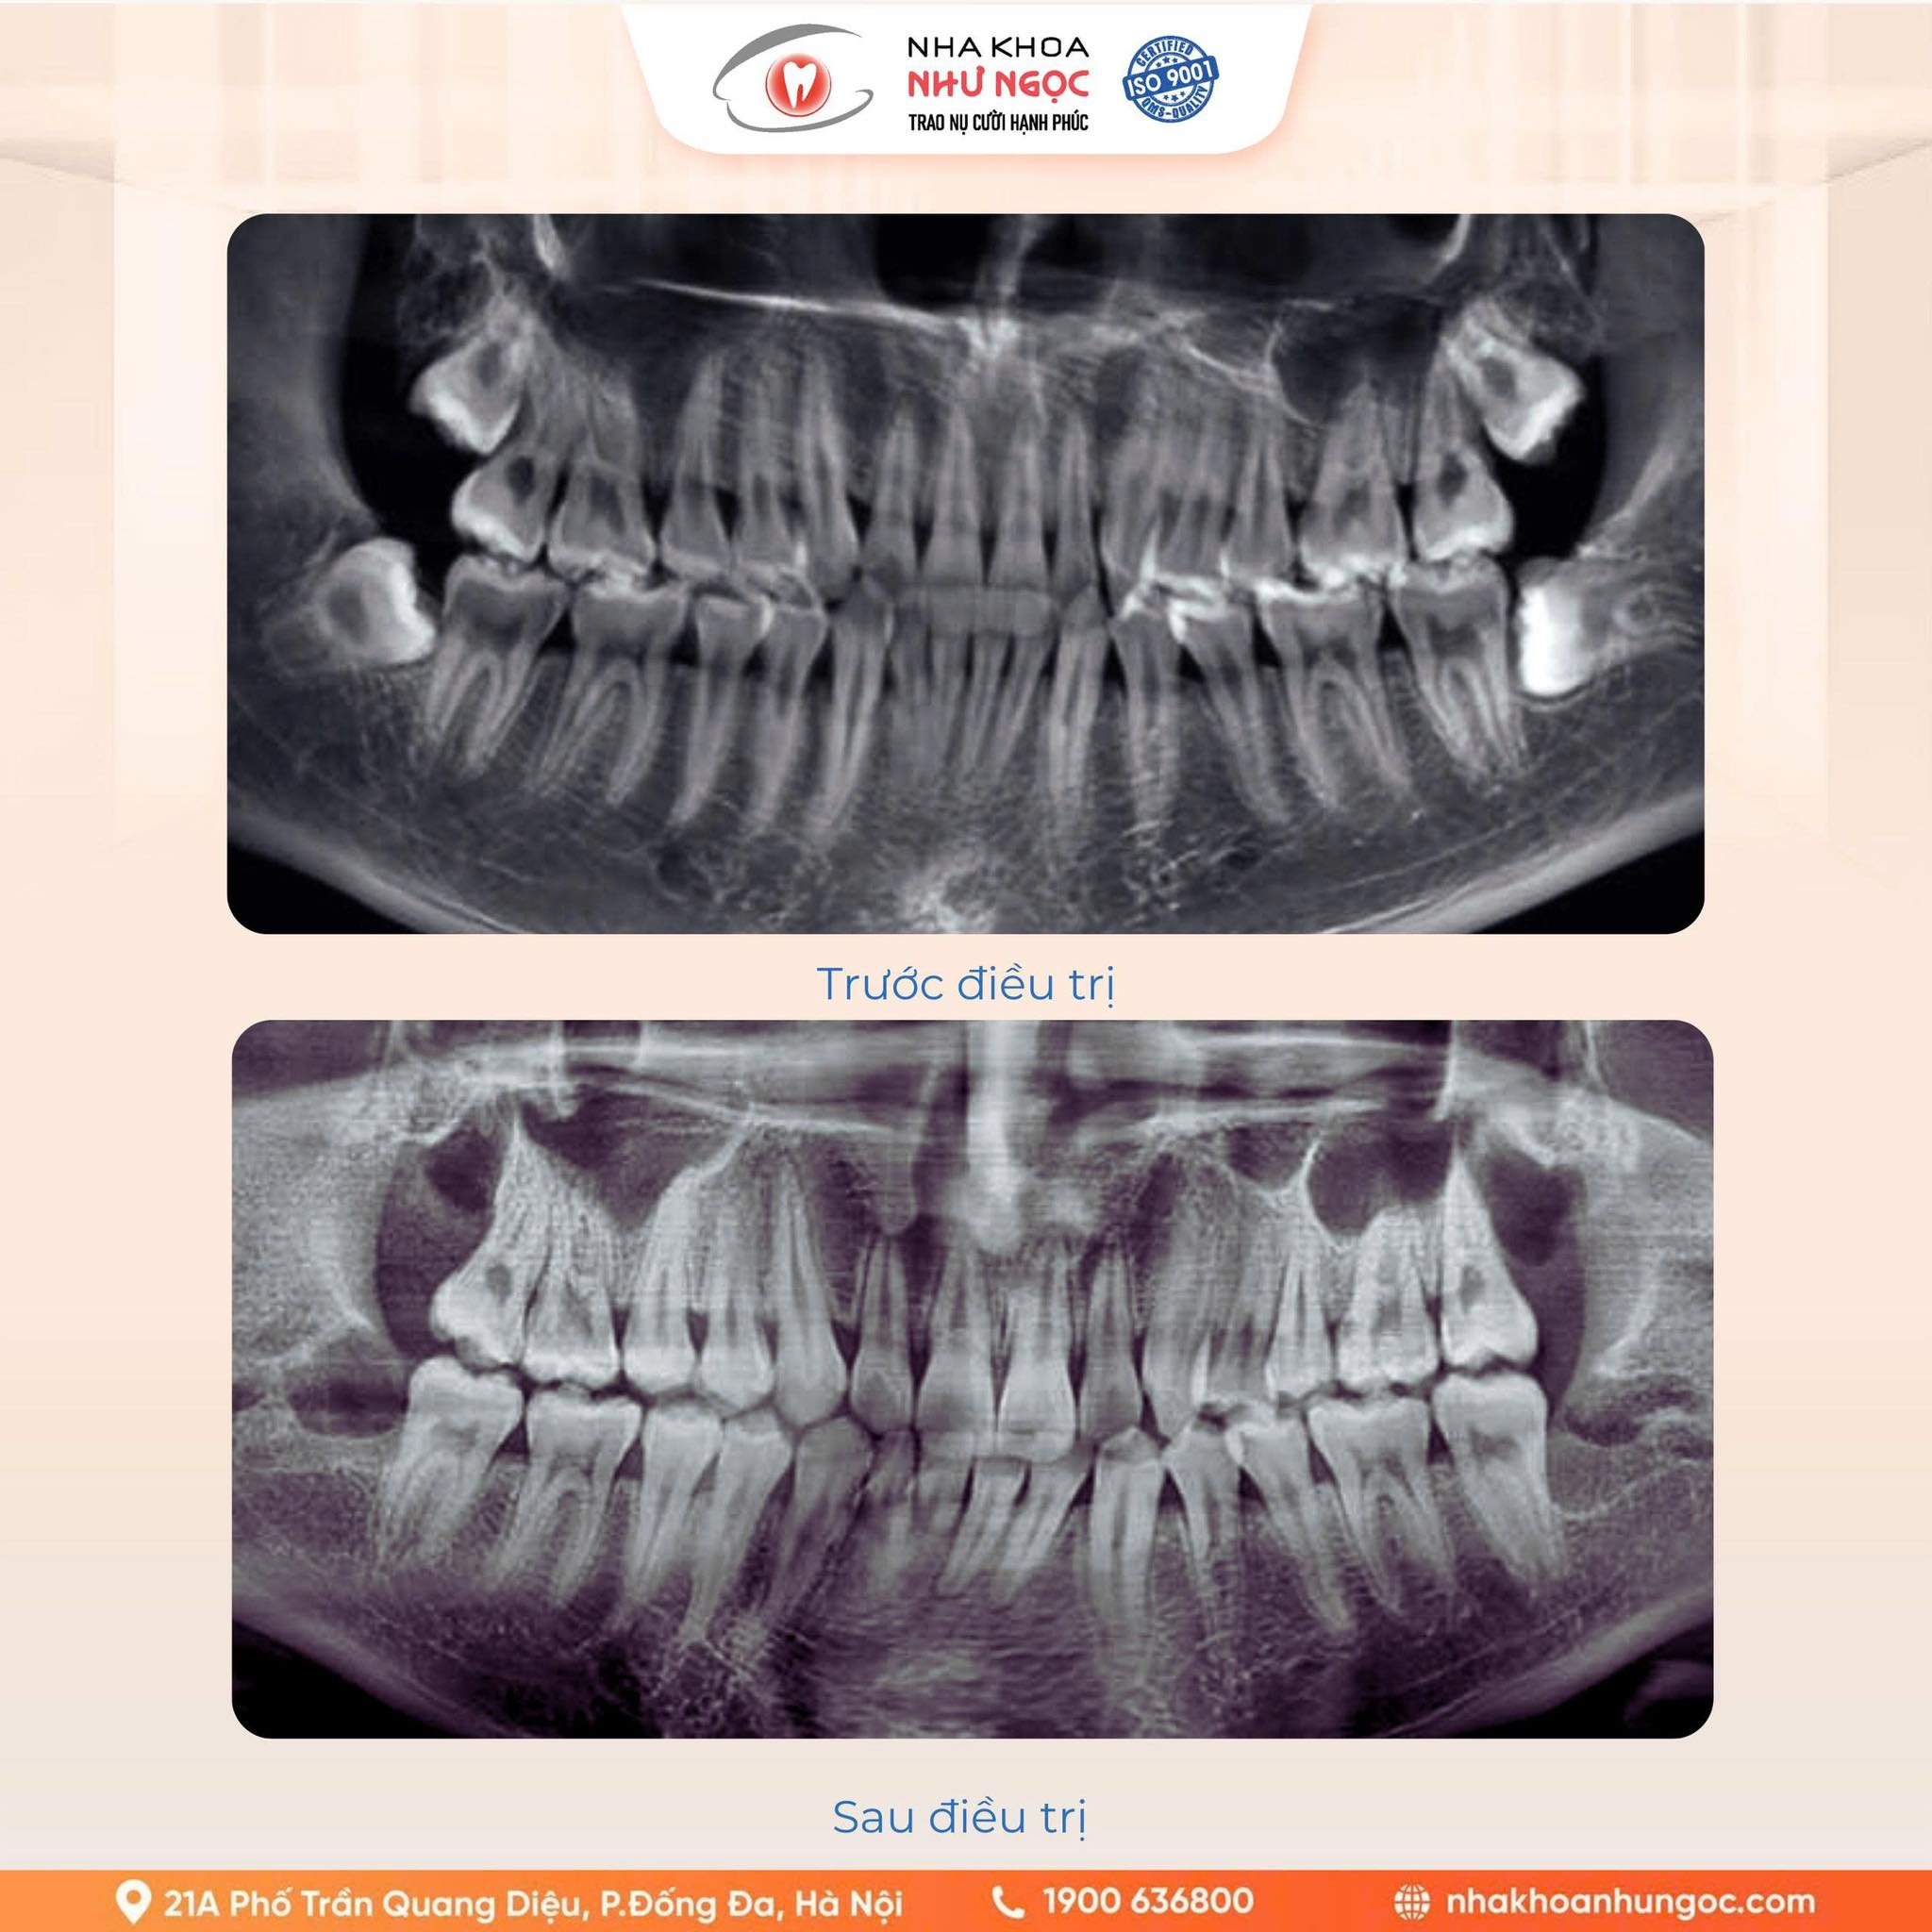

Phim chụp X – Quang trước và sau nhổ răng khôn tại Nha khoa Như Ngọc